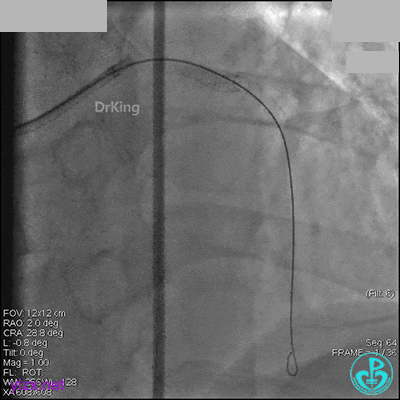

右冠脉中段充分扩张后欲植入3.5×38mm支架时,支架难以通过中远段扭曲处,且指引导管、导丝弹出飞扬。反复尝试导丝重新到达右冠脉远端时通过不顺利,局部造影剂滞留,远端血流接近3级。

右冠脉血流3级,患者无症状,终止手术。

1周后再次上台,右冠脉3级血流,3段局限性严重狭窄,内膜模糊,应该是上次操作夹层遗留下的血肿。